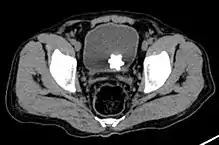

![]() ويمكن مُلاحظة حصاة على شكل نجمة في المثانة البولية بالأشعة قريبة من الحوض. ويمكن مُلاحظة حصاة على شكل نجمة في المثانة البولية بالأشعة قريبة من الحوض. | |